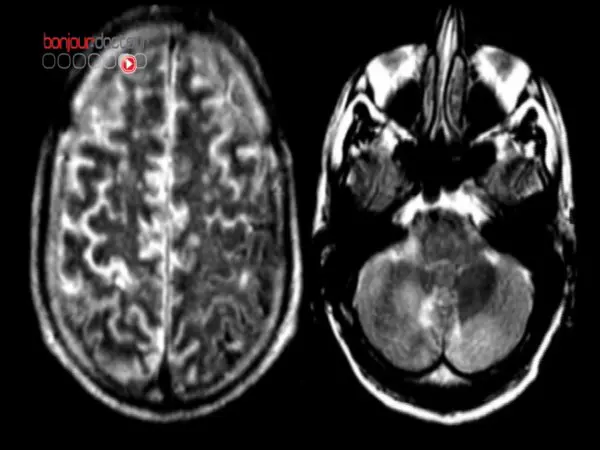

L'équipe de recherche a passé au scanner le cerveau de 24 individus et de 4 singes rhésus (un petit singe indien) pendant qu'ils regardaient le classique de Sergio Leone, avec Clint Eastwood, Le Bon, la Brute et le Truand. Une expérience cinéphilique qui a permis de découvrir que certaines zones cérébrales, assurant la même fonction chez les deux espèces, n'avaient pas la même localisation dans le cerveau. D'après les chercheurs, cette découverte serait cruciale pour mieux comprendre l'évolution.